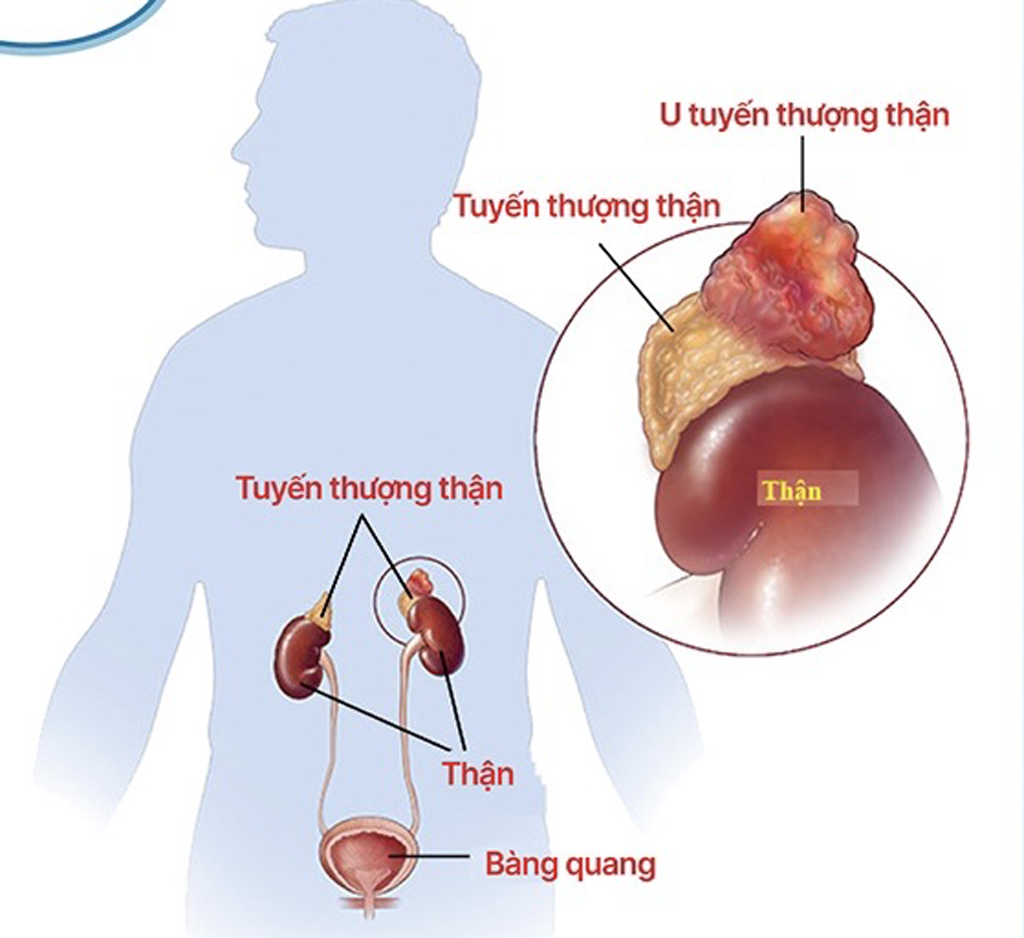

យោងតាមមន្ទីរពេទ្យកុមារជាតិ ក្រពេញ Adrenal មានពីរផ្នែក៖ ក្រពេញ Adrenal medulla រក្សាសម្ពាធឈាម និងចង្វាក់បេះដូង។ ក្រពេញ Adrenal បញ្ចេញអរម៉ូនបីប្រភេទ ដែលជួយគ្រប់គ្រងអន្តរការីមេតាបូលីស និងការឆ្លើយតបនៃប្រព័ន្ធភាពស៊ាំ សម្ពាធឈាម បរិមាណចរាចរ និងអេឡិចត្រូលីត។ ជាពិសេស ស្រទាប់កណ្តាលនៃក្រពេញ Adrenal បញ្ចេញអរម៉ូនដែលមានឥទ្ធិពលប្រឆាំងនឹងភាពតានតឹង និងប្រឆាំងនឹងការរលាក ហើយចូលរួមក្នុងការបំប្លែងជាតិស្ករ ខ្លាញ់ និងប្រូតេអ៊ីន។ ស្រទាប់ខាងក្នុងបំផុតនៃ Cortex ដើរតួក្នុងការអភិវឌ្ឍន៍ផ្លូវភេទអំឡុងពេលគភ៌។ ដូច្នេះហើយ អរម៉ូននៅក្នុងក្រពេញ Adrenal មានសារៈសំខាន់ខ្លាំងណាស់ក្នុងការថែរក្សាជីវិតមនុស្ស។

ថ្មីៗនេះ អ្នកជំងឺត្រូវបានគេរកឃើញថាមានដុំសាច់ក្នុងក្រពេញ Adrenal ទ្វេភាគីអំឡុងពេលពិនិត្យសុខភាពនៅមន្ទីរពេទ្យក្នុងស្រុក ហើយត្រូវបានផ្ទេរទៅមជ្ឈមណ្ឌលព្យាបាលរោគ Endocrinology, Metabolism, Genetics និង Molecular Therapy - មន្ទីរពេទ្យកុមារជាតិ។ នៅទីនេះ អ្នកជំងឺបានឆ្លងកាត់ការធ្វើតេស្តស៊ីជម្រៅ អ៊ុលត្រាសោន និងកាំរស្មីអ៊ិច ដើម្បីកំណត់យ៉ាងត្រឹមត្រូវនូវដុំសាច់។